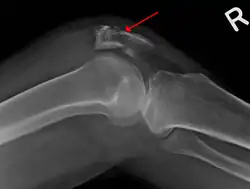

| A fracture of the patella seen on a lateral view | |

The patella can break in various ways depending on the way it is injured, and into two or more pieces.[1] Types include transverse, the most common, with one fracture line;[5] marginal; osteochondral; and the rare vertical type, or stellate, where a direct compression force gives rise to a comminuted pattern.[5][7] Patella fractures can be further classified as displaced, where the broken ends of bone do not line up correctly and separate by more than 2mm, or undisplaced and stable where pieces of bone remain in contact with each other.[1][7] If fragments of patella bone stick out from the skin it is known as an open patella fracture, and closed if the overlying skin is intact.[1]

Transverse fracture of patella -

Comminuted fracture of patella -

Osteochondral fracture of patella -

Vertical patella fracture